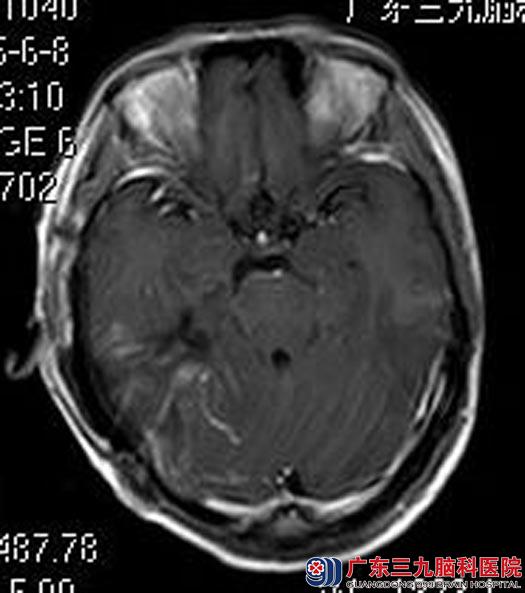

完善各项检查后,由鲁明主任主刀,在全麻下行右侧中后颅窝占位切除术,术中显微镜下见肿瘤质软,呈灰白色,血供丰富,超声吸引器瘤内切除部分肿瘤,肿瘤沿岩骨向后长入后颅窝,可见肿瘤内侧滑车神经、小脑幕,电磁刀切开并切除小脑幕约1cm,见颞骨岩部、斜坡肿瘤组织,肿瘤与周围关系紧密,牵拉抬起肿瘤,向下见肿瘤与滑车、三叉神经及后组神经上缘粘连,分离后予以切除。手术顺利,术后黄女士未出现神经损害症状,现已康复出院。术后病理结果:血管周细胞瘤(相当于WHO II 级)。

▲手术后